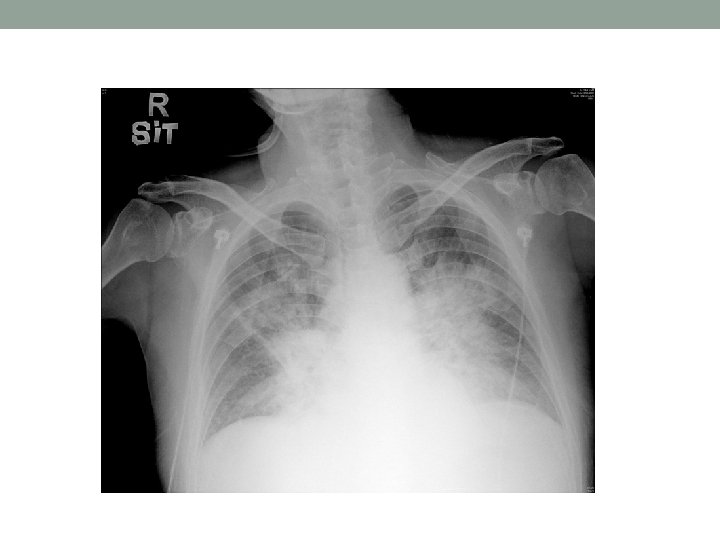

Day 1 • Presentation: • Polyuria and polydipsia for a few days • Chest discomfort and SOB for 2 -3 days • AED: • No fever • H’stix high and urine ketone +ve • ABG: BE -12. 3 • CXR-congested lungs • ECG-sinus tachycardia, no obvious ST/T changes • To ICU for DKA

Upon ICU admission • Afebrile • BP 105/76 • HR 140 • Sa. O 2 100% on 100% NRM • Overweighted • Respiratory distress+ • Alert and obey command • JVP-elevated • Chest-diffuse crepitations • Abdomen-soft, non-tender